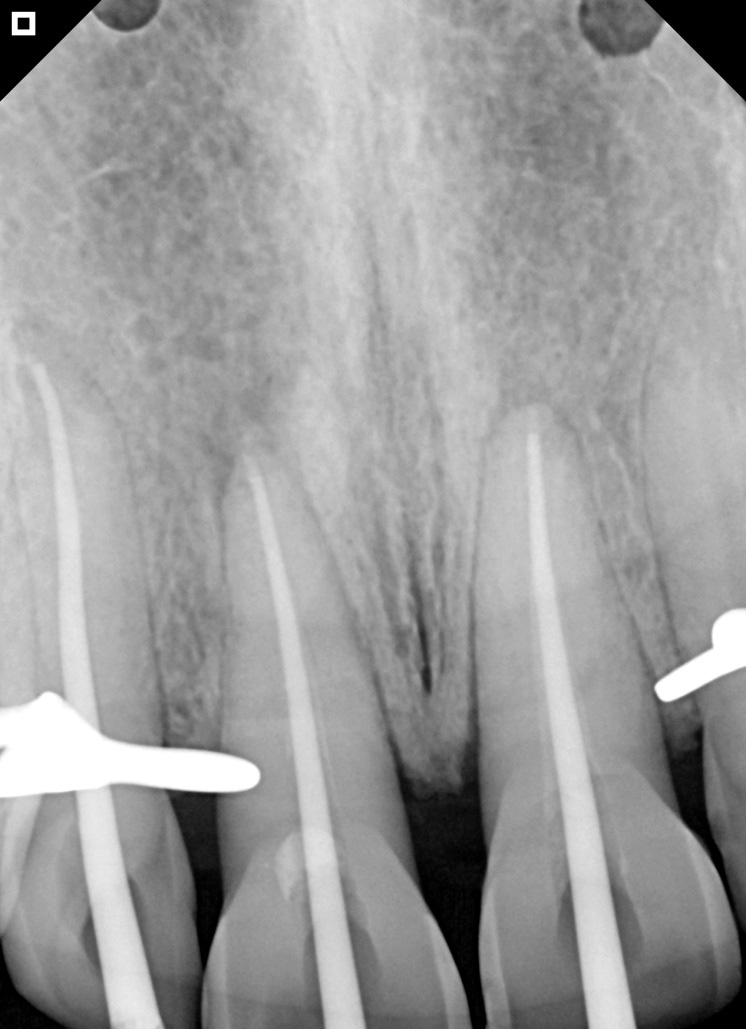

Radiography immediately after application of Bio-C Temp.